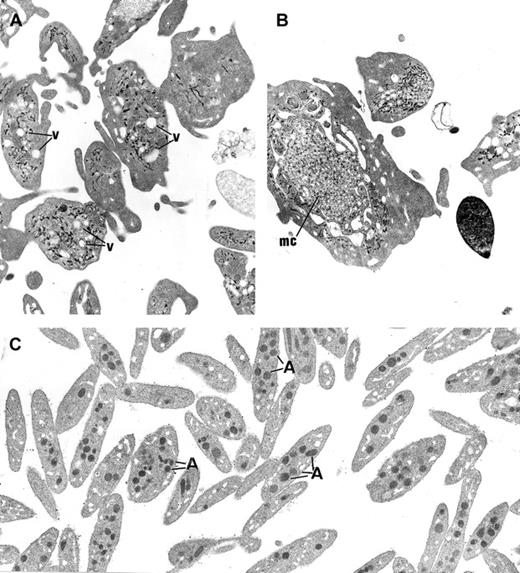

The platelets from the 3 children displayed similar ultrastructure. Platelet size was heterogeneous, and many platelets were larger than a red blood cell or a small lymphocyte. The most striking morphologic abnormality was the lack of normal α-granules and prominent vacuolization of the cytoplasm (Figure3A). Membrane complexes, which represent abnormally distributed intracellular membrane, were also observed (Figure 3B).

Ultrastructure of platelets.

(A) In GPS, normal α-granules are absent from the platelets and replaced by vacuolar structures (v) the size of normal α-granules. (B) Platelets of large size displaying membrane complex (mc) and devoid of normal α-granules are encountered. (C) Platelets from a normal subject are smaller and display conspicuous α-granules (A). (Panels A-C, original magnification × 10 500.)